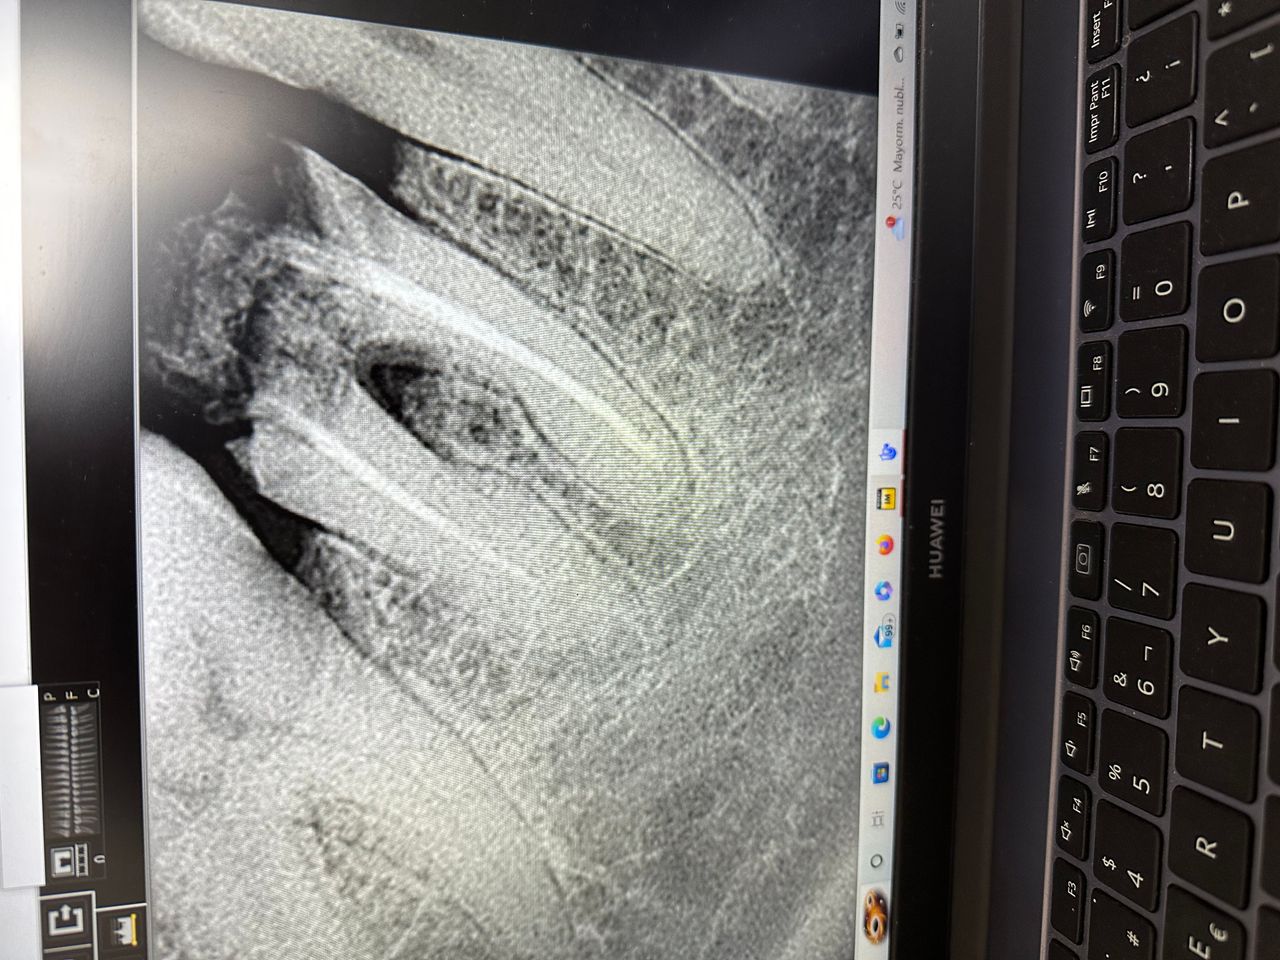

Galería

Muy delicada. Explica muy bien. Moderna y actualizada con tecnología de punta y el detalle de mostraré tu dentadura antes del procedimiento y estaría genial que lo volviera a hacer al final del procedimiento.